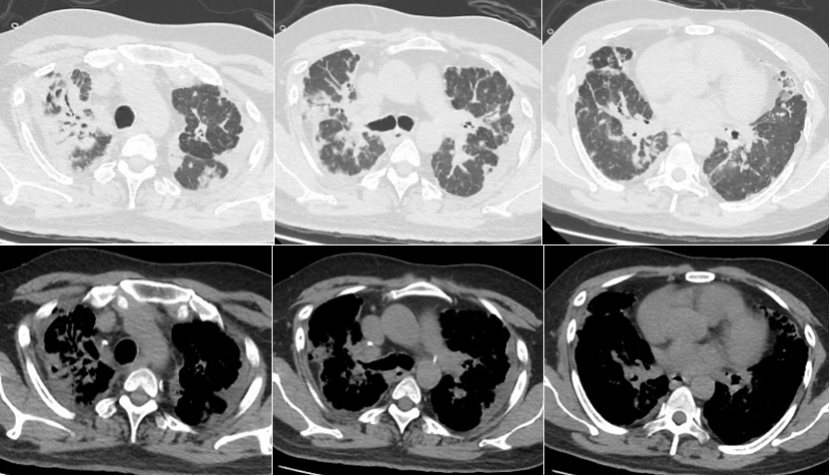

2021年12月27日胸部CT:双肺弥漫网格影、斑片影及结节影,双侧胸膜增厚,双肺间质性肺炎可能,双侧胸膜增厚,双侧少许胸腔积液(图16)。

先后从事电焊工、油漆工、蒸馒头等工作;有吸烟史;无明确基础病。咳嗽、少痰、进行性加重的活动后呼吸困难,间断发热,单用抗感染治疗时有效时无效,抗感染联合激素治疗有效,停用激素或激素减量后可复发加重,加量后有好转趋势。双上肺干鸣音;前胸、背部多发毛囊炎;双下肢可见散在红色丘疹,双足底可见片状脱屑。实验室检查:WBC/NEU计数增多,炎症指标水平增高,PCT正常;Ⅱ型呼吸衰竭、肺动脉高压;自身抗体/肿瘤标志物无明确指向;无明确病原学证据;BALF细胞分类以中性粒细胞为主,无淋巴细胞及嗜酸粒细胞增多;影像学提示小叶间隔增厚、弥漫网格影及结节影,上叶为著,双侧胸膜增厚。

超声引导下经皮肺穿刺(2021年12月28日):右上肺尖部胸膜及肺组织低回声处进行穿刺,穿取组织条3小条。结合影像学、组织学及特殊染色,符合PPFE,合并较多碳末沉积,局灶淋巴细胞聚集;免疫组化结果:CK(AE1/AE3)(+),KP-1(+),LCA(+),CK5/6(+),TTF-1(+);特殊染色结果:Masson(局灶+),PAS(-),弹力纤维(++),铁染色(-),银染(-)。2021年12月26日至2022年1月1日:头孢哌酮舒巴坦3 g q8h ivgtt。2021年12月27-31日:甲强龙40 mg qd ivgtt。2022年1月1日至2022年1月7日:泼尼松20 mg qd po。